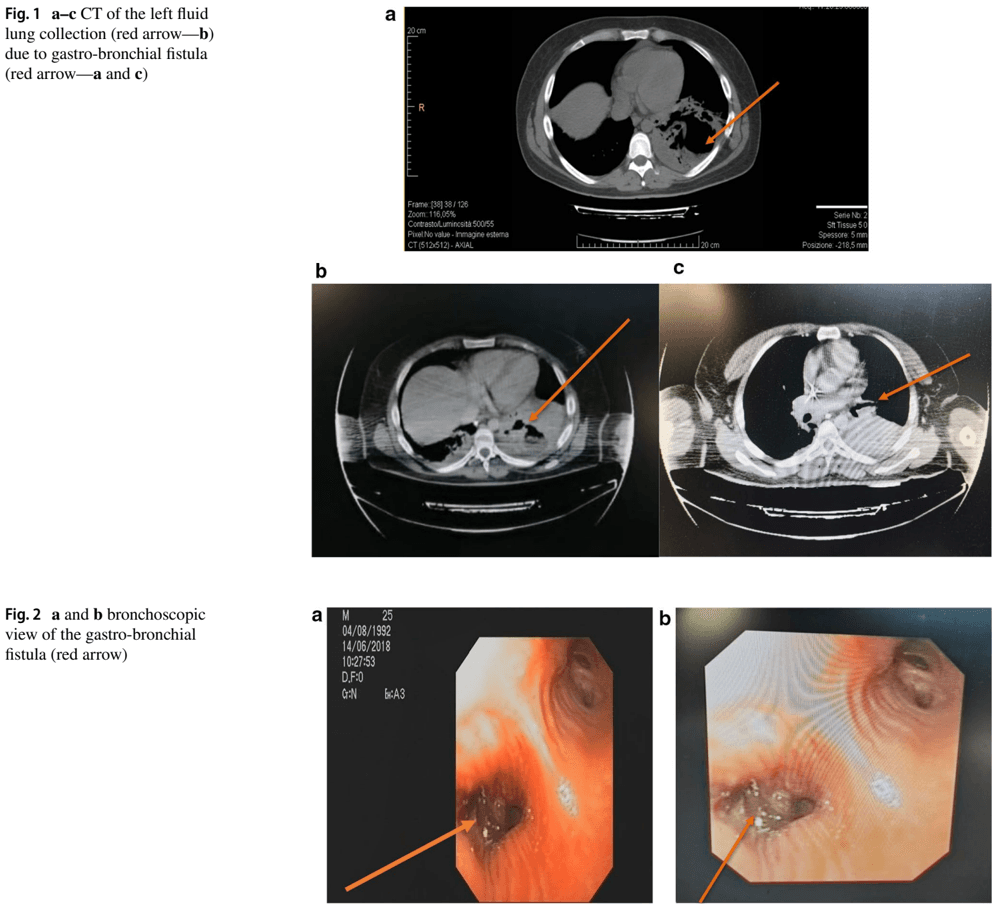

Stemming the Leak: A Novel Treatment for Gastro-Bronchial Fistula

F. M. Mongardini, C. Cacciatore, A. Catauro, F. Maglione, F. Picardi, A. Lauro, C. Gambardella, A. Allaria, L. Docimo, Digestive Diseases and Sciences, 2022